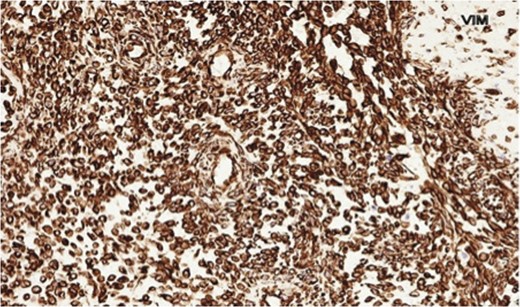

The histopathology demonstrated that the breast was partially replaced by a partly cystic and partly solid necrotic lesion. The cystic cavity contained blood clots. A microscopic examination showed an atypical undifferentiated spindle cell lesion with a fascicular architecture, pleomorphism and marked mitotic activity with areas of ulceration and necrosis (Figs 1 and 2). The initial set of immunostains performed showed that tumour cells were negative for cytokeratins (Fig. 3), S100 and LCA. The tumour cells showed diffuse and strong vimentin positivity (Fig. 4). Further immunocytochemical labelling showed weak expression of CD99, patchy strong expression of CD10 and patchy weak expression of smooth muscle actin. Cytokeratins (CAM 5.2) and EMA were expressed and there was no tumour-specific expression of CD34, desmin or myogenin. Fluorescent In-situ hybridization analysis failed to demonstrate evidence of a t(x:18) translocation using the LYS-SYT break apart probe. The diagnosis of a Grade 3 undifferentiated spindle cell sarcoma was made and although the tumour was reported to have a clear resection margin (5 mm) in most areas, the presence of necrosis and granulation tissue reaching the deep margin made the status of the margin uncertain.

Staging computed tomography scan demonstrated left axillary lymphadenopathy and a small left-sided basal effusion. Following discussion of the case at the multidisciplinary meeting, radical completion mastectomy was recommended. In addition, she underwent adjuvant radiotherapy. Reconstruction was with a split thickness skin graft by the plastic surgery team prior to her radiotherapy treatment (Fig. 5).